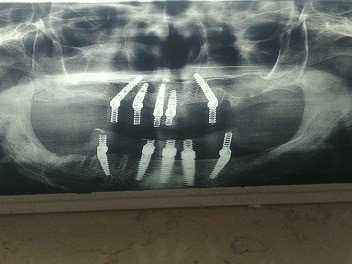

מקרים אחרים בהם מקובל להעמיס על השתלים מייד לאחר ההשתלה הם המקרים בהם משקמים לסת שלמה על ידי שתלים, בעיקר השיטה של 4 ALL ON .

בשיטה זו מעמיסים על השתלים כתרים של לסת שלמה ביום ההשתלה.

עליהו לדאוג במקרה זה לשתלים ארוכים ויציבים, שיוכלו לשאת את העומס, לא לזוז , ולהתקבע בעצם הלסת.

במקרים המתאימים, השיטה מצליחה בצורה טובה, והכתרים הזמניים שביצענו ביום ההשתלה נכנסים לתפקוד מיידי.

לכן נקראת השיטה השתלת שיניים ביום אחד. ביום אחד מבוצעים השתלים, ובערבו של יום, מותקנים עליהם כתרים זמניים.